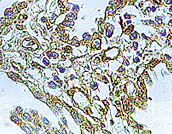

WB/IH/IP技術(shù)